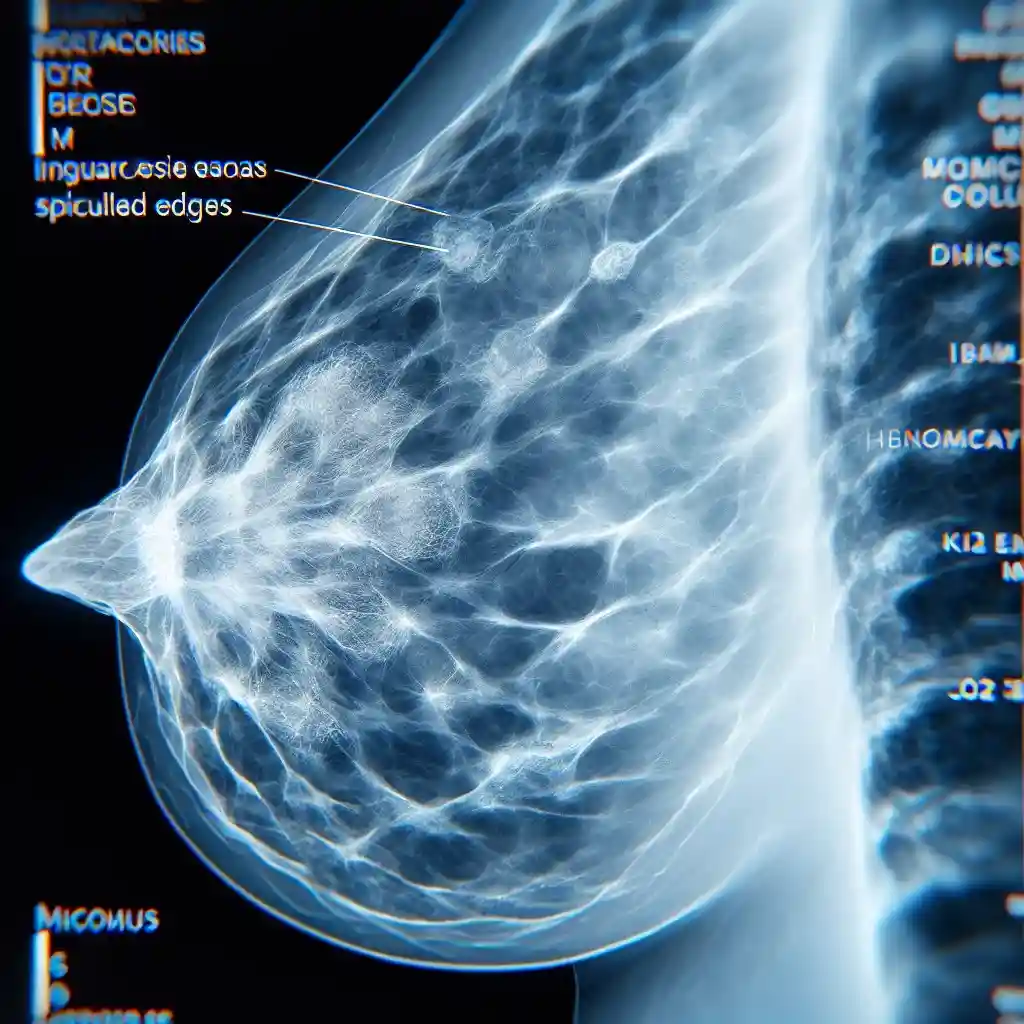

Как выглядит рак на маммографии?

Рак на маммографии обычно проявляется в виде участков с нечеткими, зазубренными контурами, плотных теней и микрокальцинатов неправильной формы. Опытный врач способен отличить эти признаки от доброкачественных изменений.